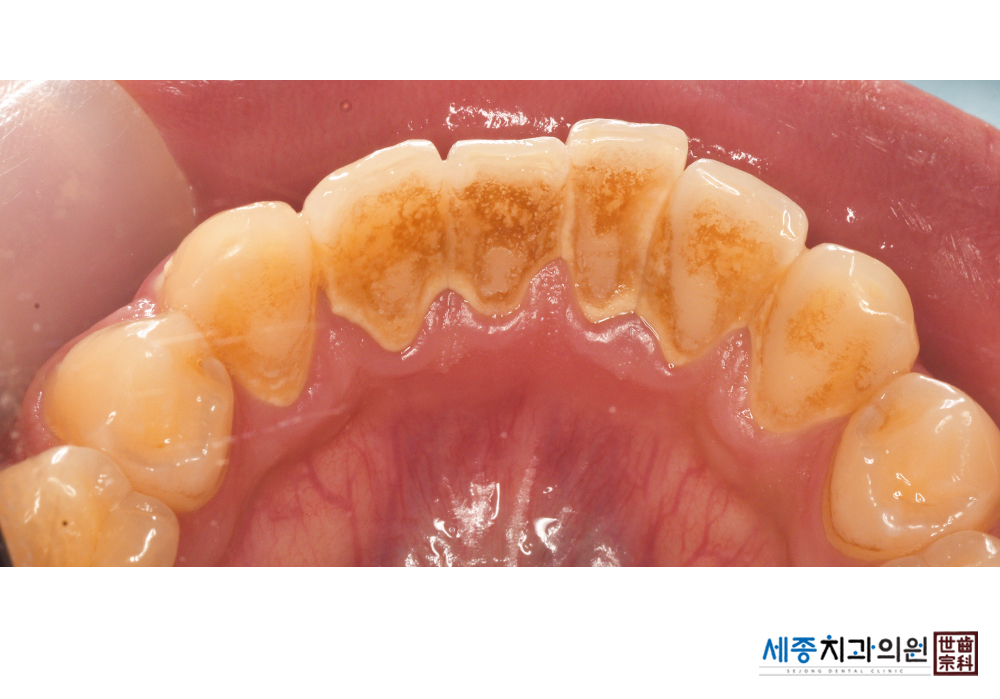

[스케일링] 치주질환 예방 스케일링

치료후 : 2020-01-20

가글마취&저주파 스켈러를 사용한 스케일링